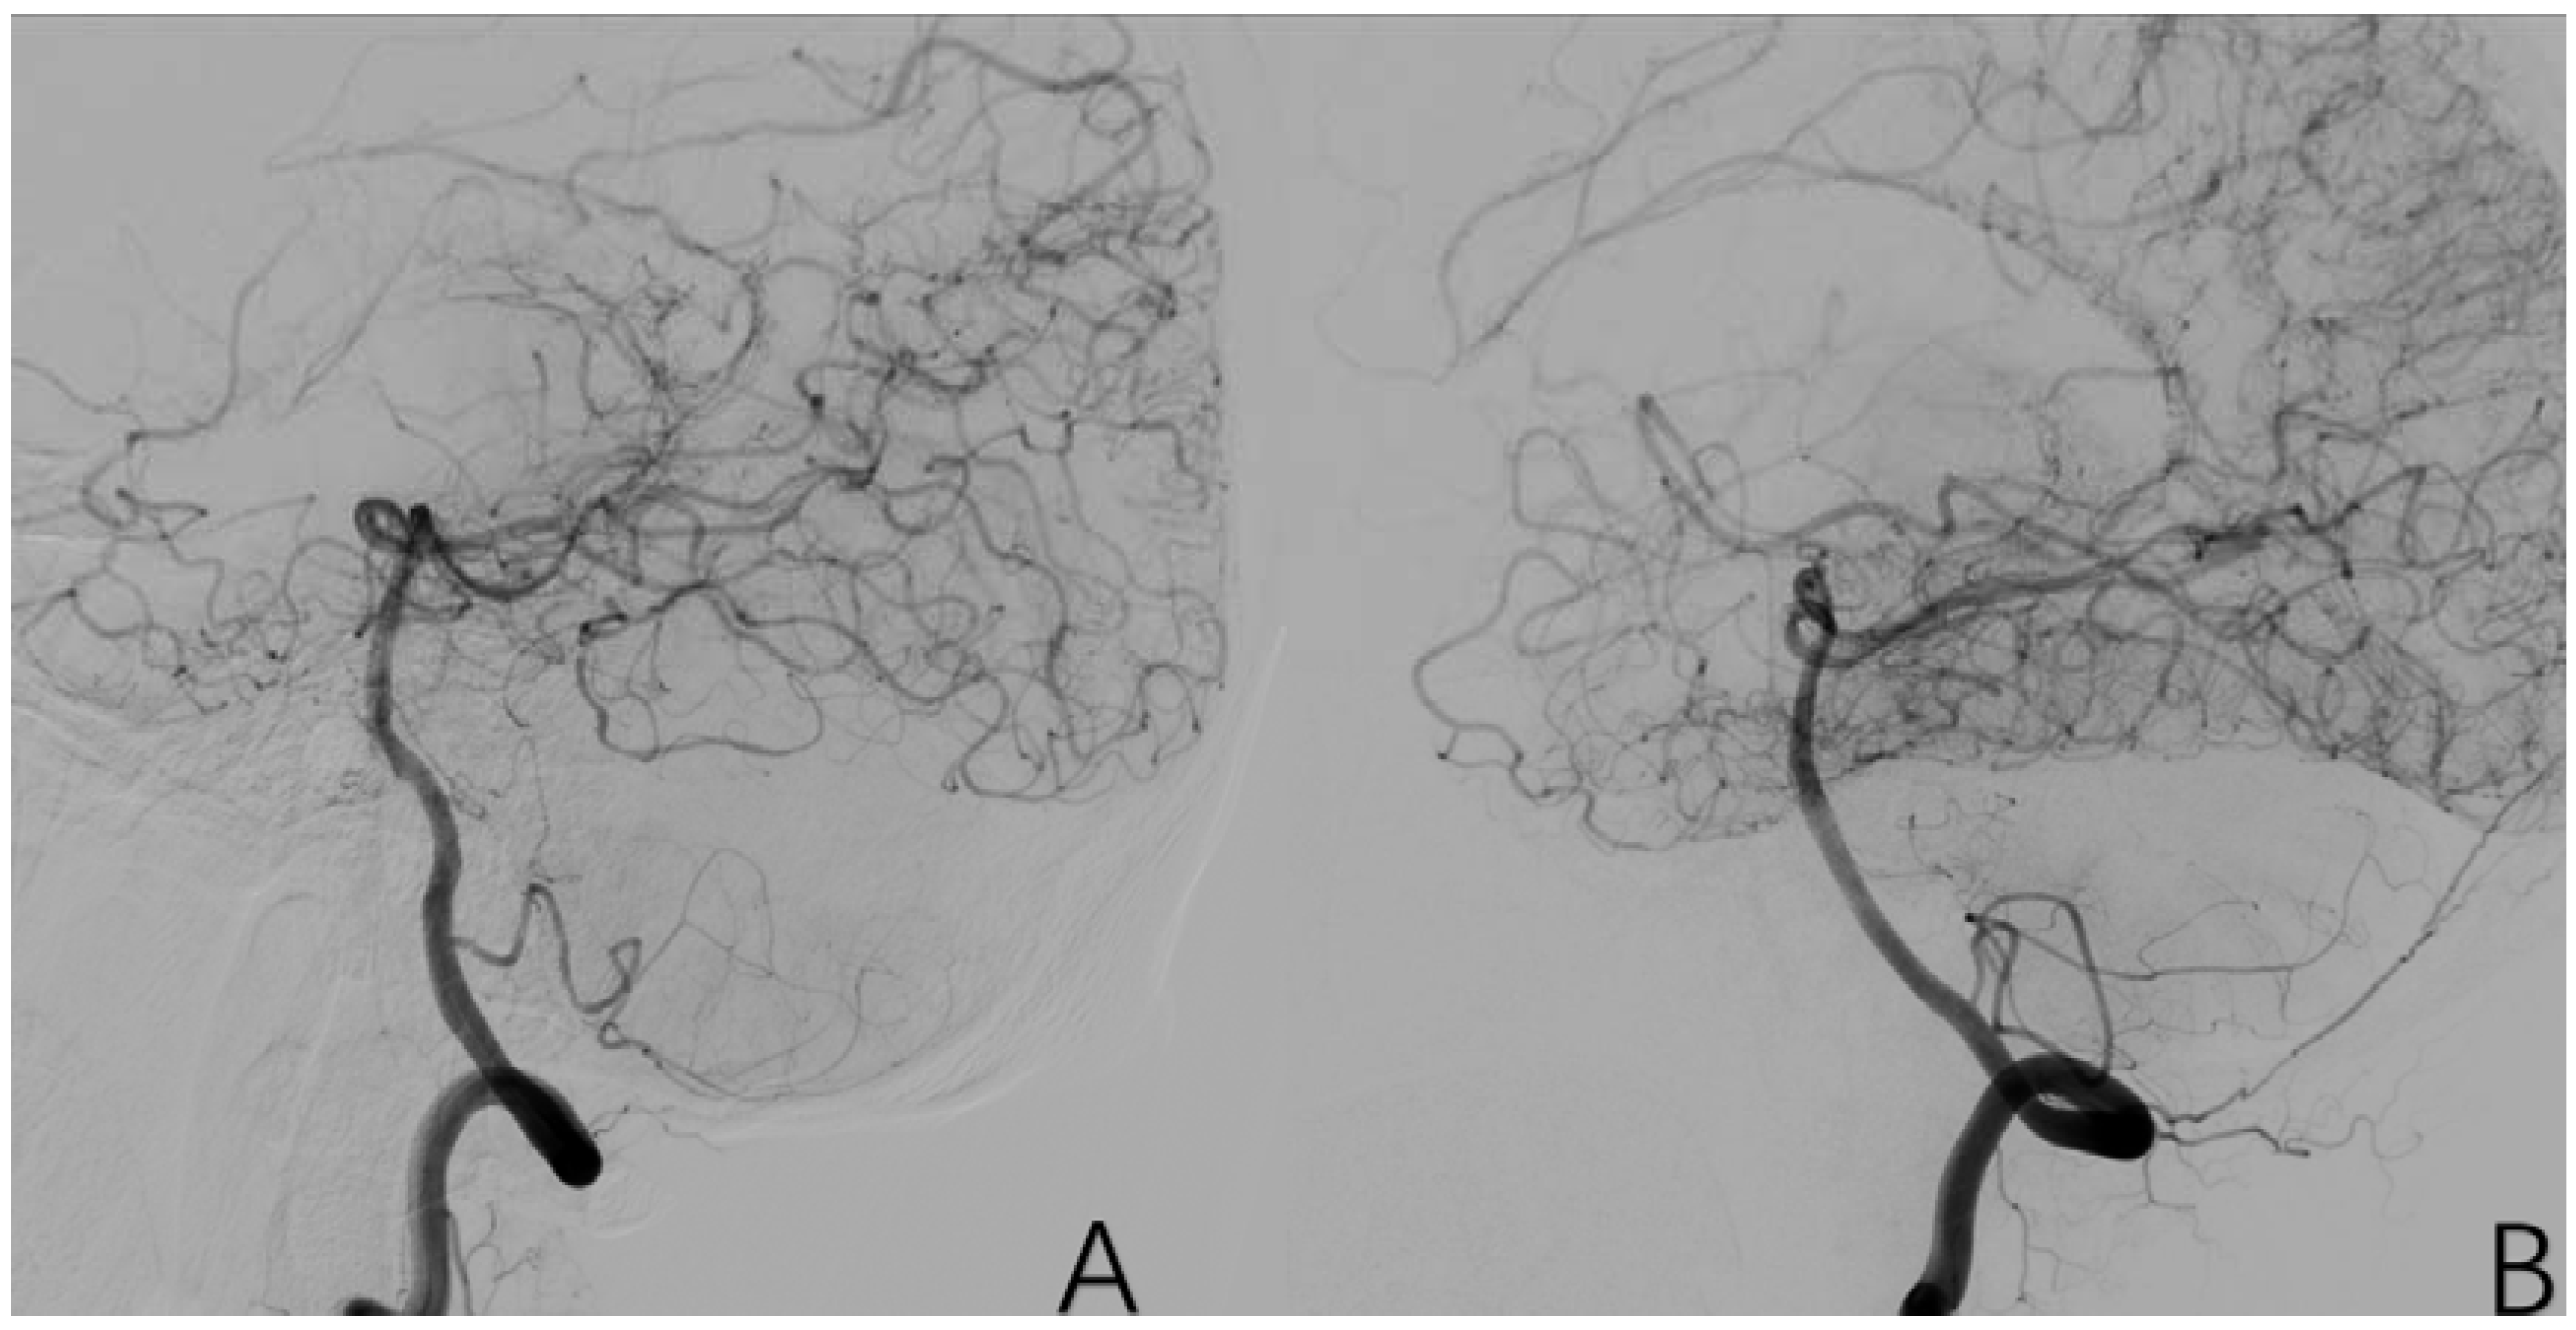

2.3.12. Factor 7 Extracranial Arterial Compensation